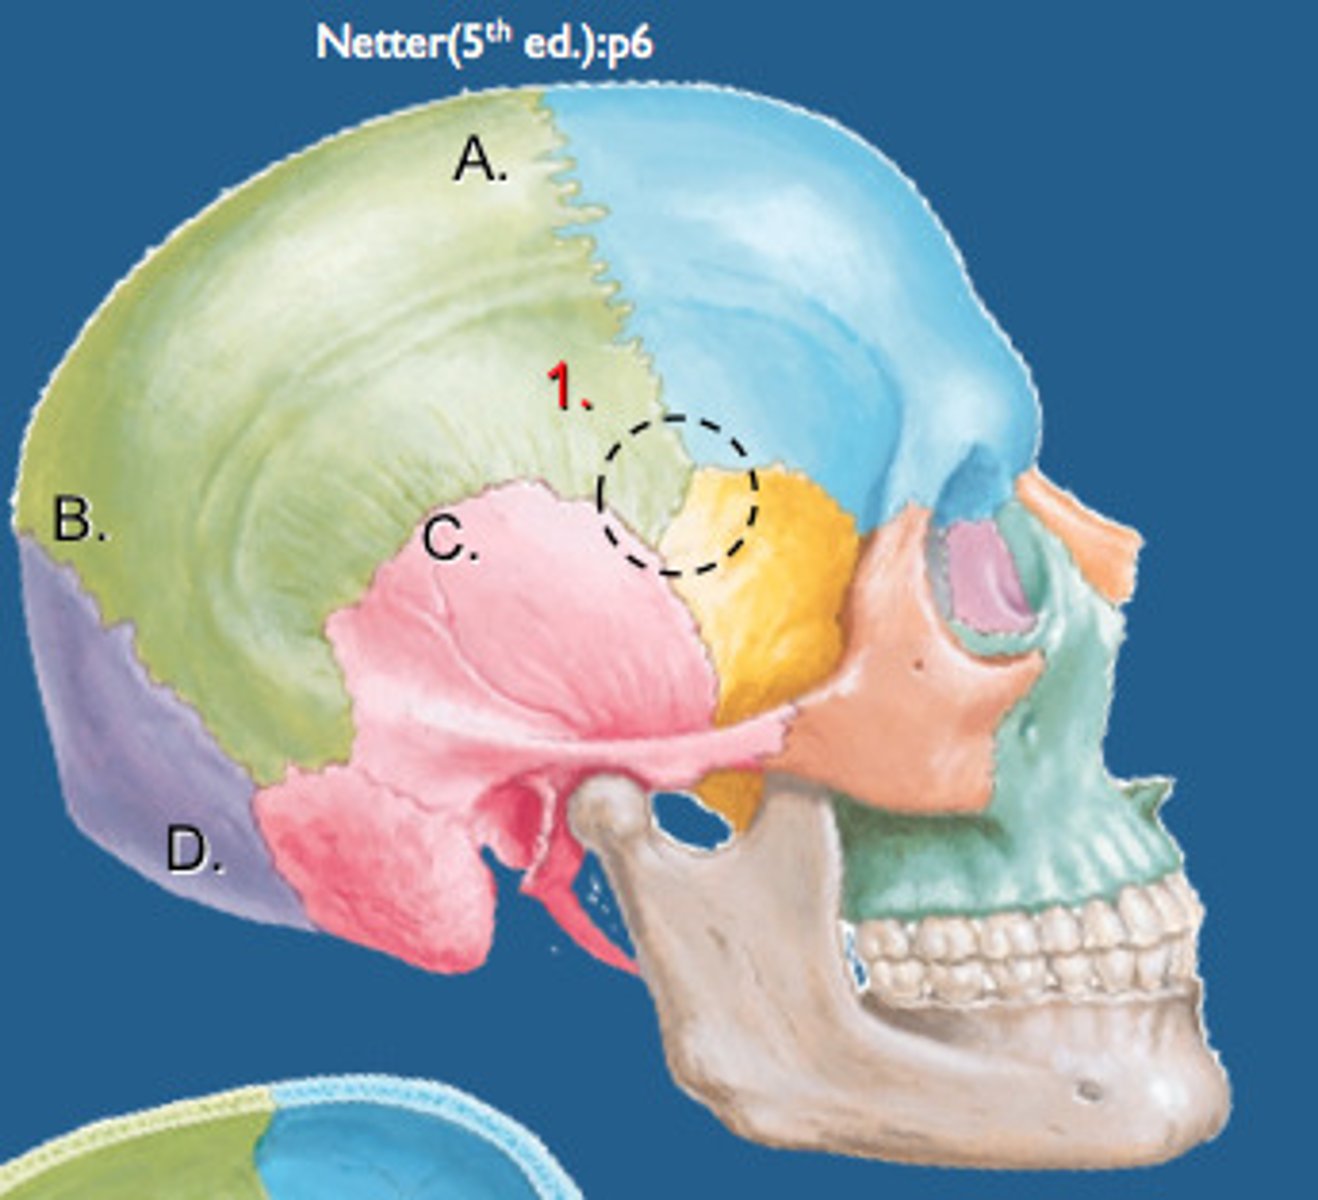

What is B

frontal bone

What is A

ethmoid

What is C

sphenoid

what is D

Palatine

What is E

Zygoma

What is F

Maxilla

pterion